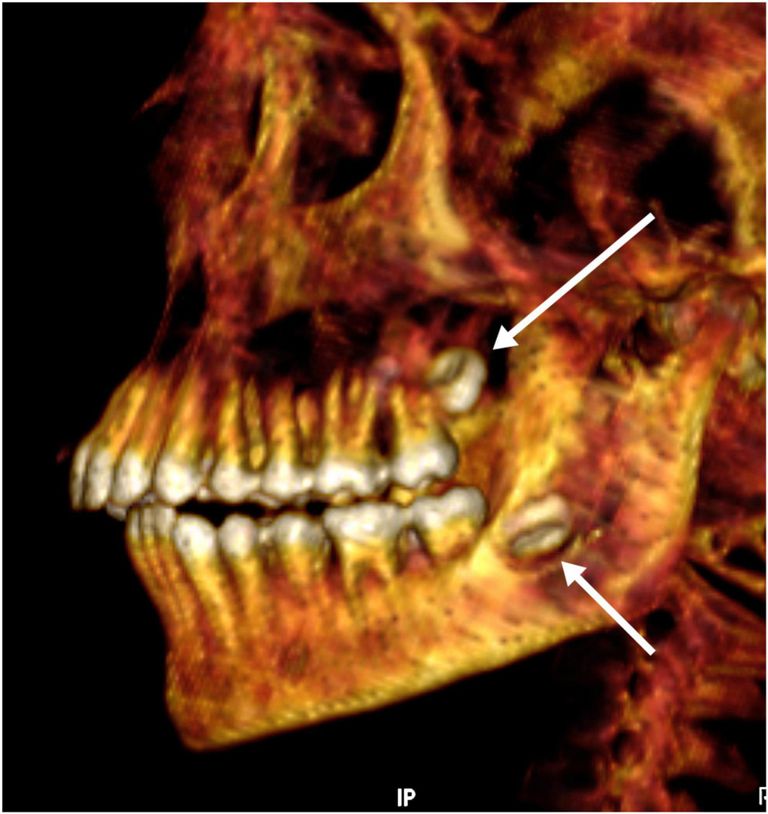

كم عمر الصبي؟

يتراوح ما بين 14: 15 عامًا.

بالاطلاع تبين أن التحنيط كان على مستو عال، خاصةً مع إزالة المخ من الأنف والأحشاء من فتحة أسفل البطن، ووضع الحشوات والمواد الراتنجية.